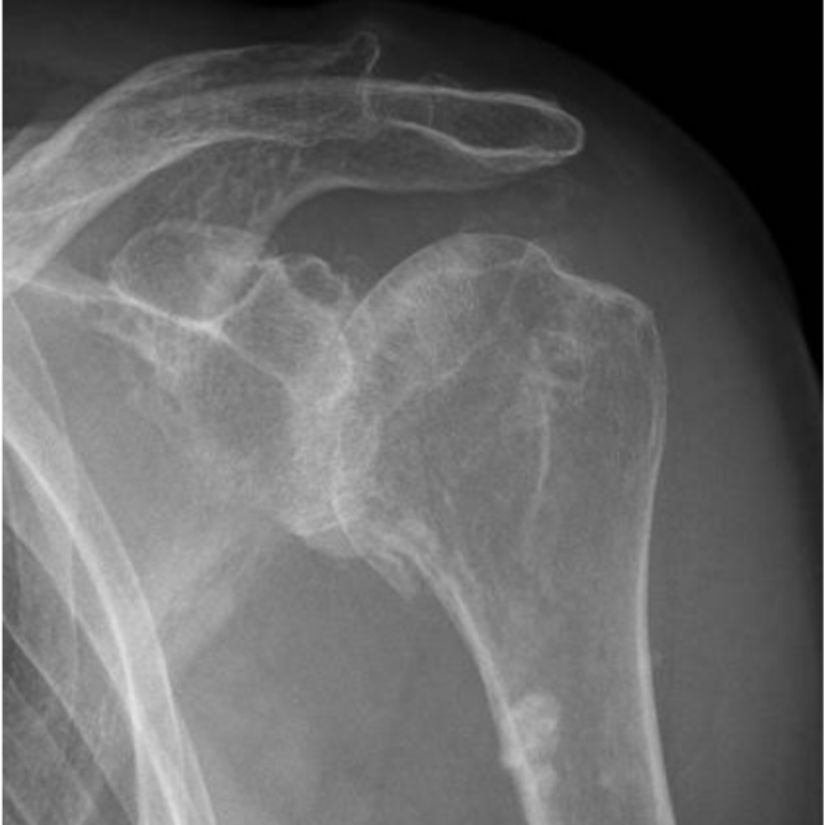

Een röntgenfoto geeft zekerheid over de diagnose. Daarop kunnen we zien dat de ruimte tussen de kop en kom smaller is dan normaal. Dat is een teken dat het kraakbeen op de botten is weggesleten. Verder kunnen we zien of er extra bot is aangegroeid (osteofyten).

Röntgenfoto van een schouder met artrose. Het is ‘bot-op’bot’.

We kunnen de mate van slijtage een ‘score’ geven op de röntgenfoto. Van klasse 1 (bijna geen slijtage) tot klasse 4 (vrijwel volledige slijtage van het kraakbeen).